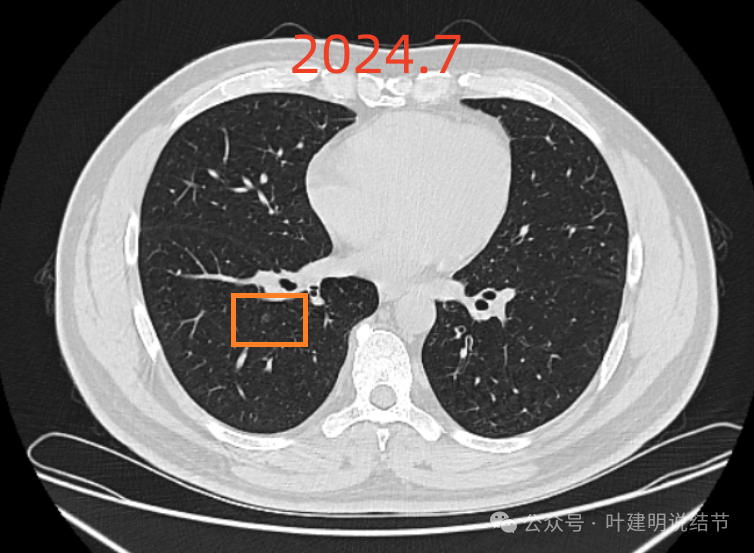

患者2019年7月体检首次发现右肺2处磨玻璃,大小5毫米,某医科大学附属第一医院随访4年,2024年7月复查右肺散在磨玻璃,和2023年12月份复查变化不大。备注:父亲肺癌晚期去世。辅检:23-12-10肺CT诊断结论 右肺散在磨玻璃结节,较大两枚高危倾向,对比2023-04-02CT部分新增,建议密切复查。两肺增殖钙化灶。24-7-14肺CT诊断结论左肺下叶细支气管炎,请结合临床及复查。右肺散在磨玻璃结节,对照2023-12-10CT大致相仿,建议定期复 查。两肺少许增殖钙化灶。今为咨询特来就诊。

2024年7月时右下病灶感觉比2023年12月的反而略有好转,当然这应该是扫描层面的关系,但至少说明与2022年5月比并无明显进展的。

1、结节性质:右肺中叶以及下叶磨玻璃密度结节,整体轮廓清楚,瘤肺边界清,随访持续存在,是要考虑肿瘤范畴的。我分别截图了2022年5月、2023年12月以及2024年7月的最明显层面,两处病灶均基本没有任何变化进展。而且灶内并无实性成分,应该考虑肺泡上皮增生或不典型增生可能性为大,但由于影像表现存在交叉,纯磨既可以是前面我说的这两者,也可以是原位癌或微浸润性腺癌,甚至浸润性腺癌贴壁型也会是这样的表现,但不管最后是什么,只要纯磨密度风险就是低的,随访不至于延误病情,也不会有不同预后,都是局部完整切除就治愈。